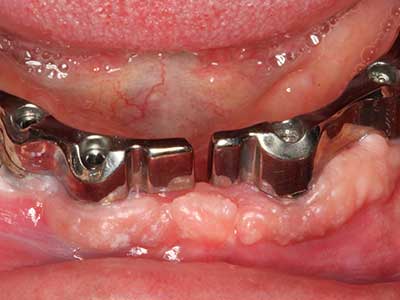

Abb. 15: Die röntgenologische Ein-Jahres-Kontrolle zeigt stabile Verhältnisse des Knochenniveaus.

Abb. 16: Auch intraoral stabile Verhältnisse mit Einbettung der Implantate in keratinisierter Gingiva.